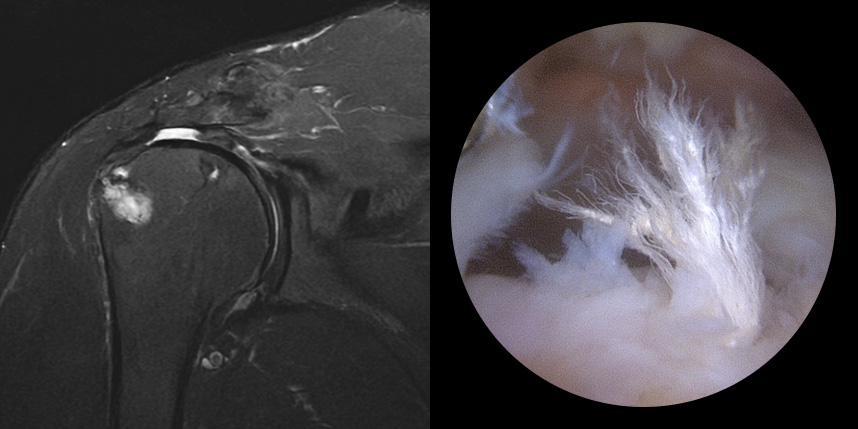

일열 봉합술

브릿지 봉합술

접촉면접과 힘줄

부착 압력이 높습니다.

초기,중기,말기 파열에

주로 사용됩니다.

상대적으로

재파열율이 낮습니다.

* 환자에게 받은 소중한 자료입니다.